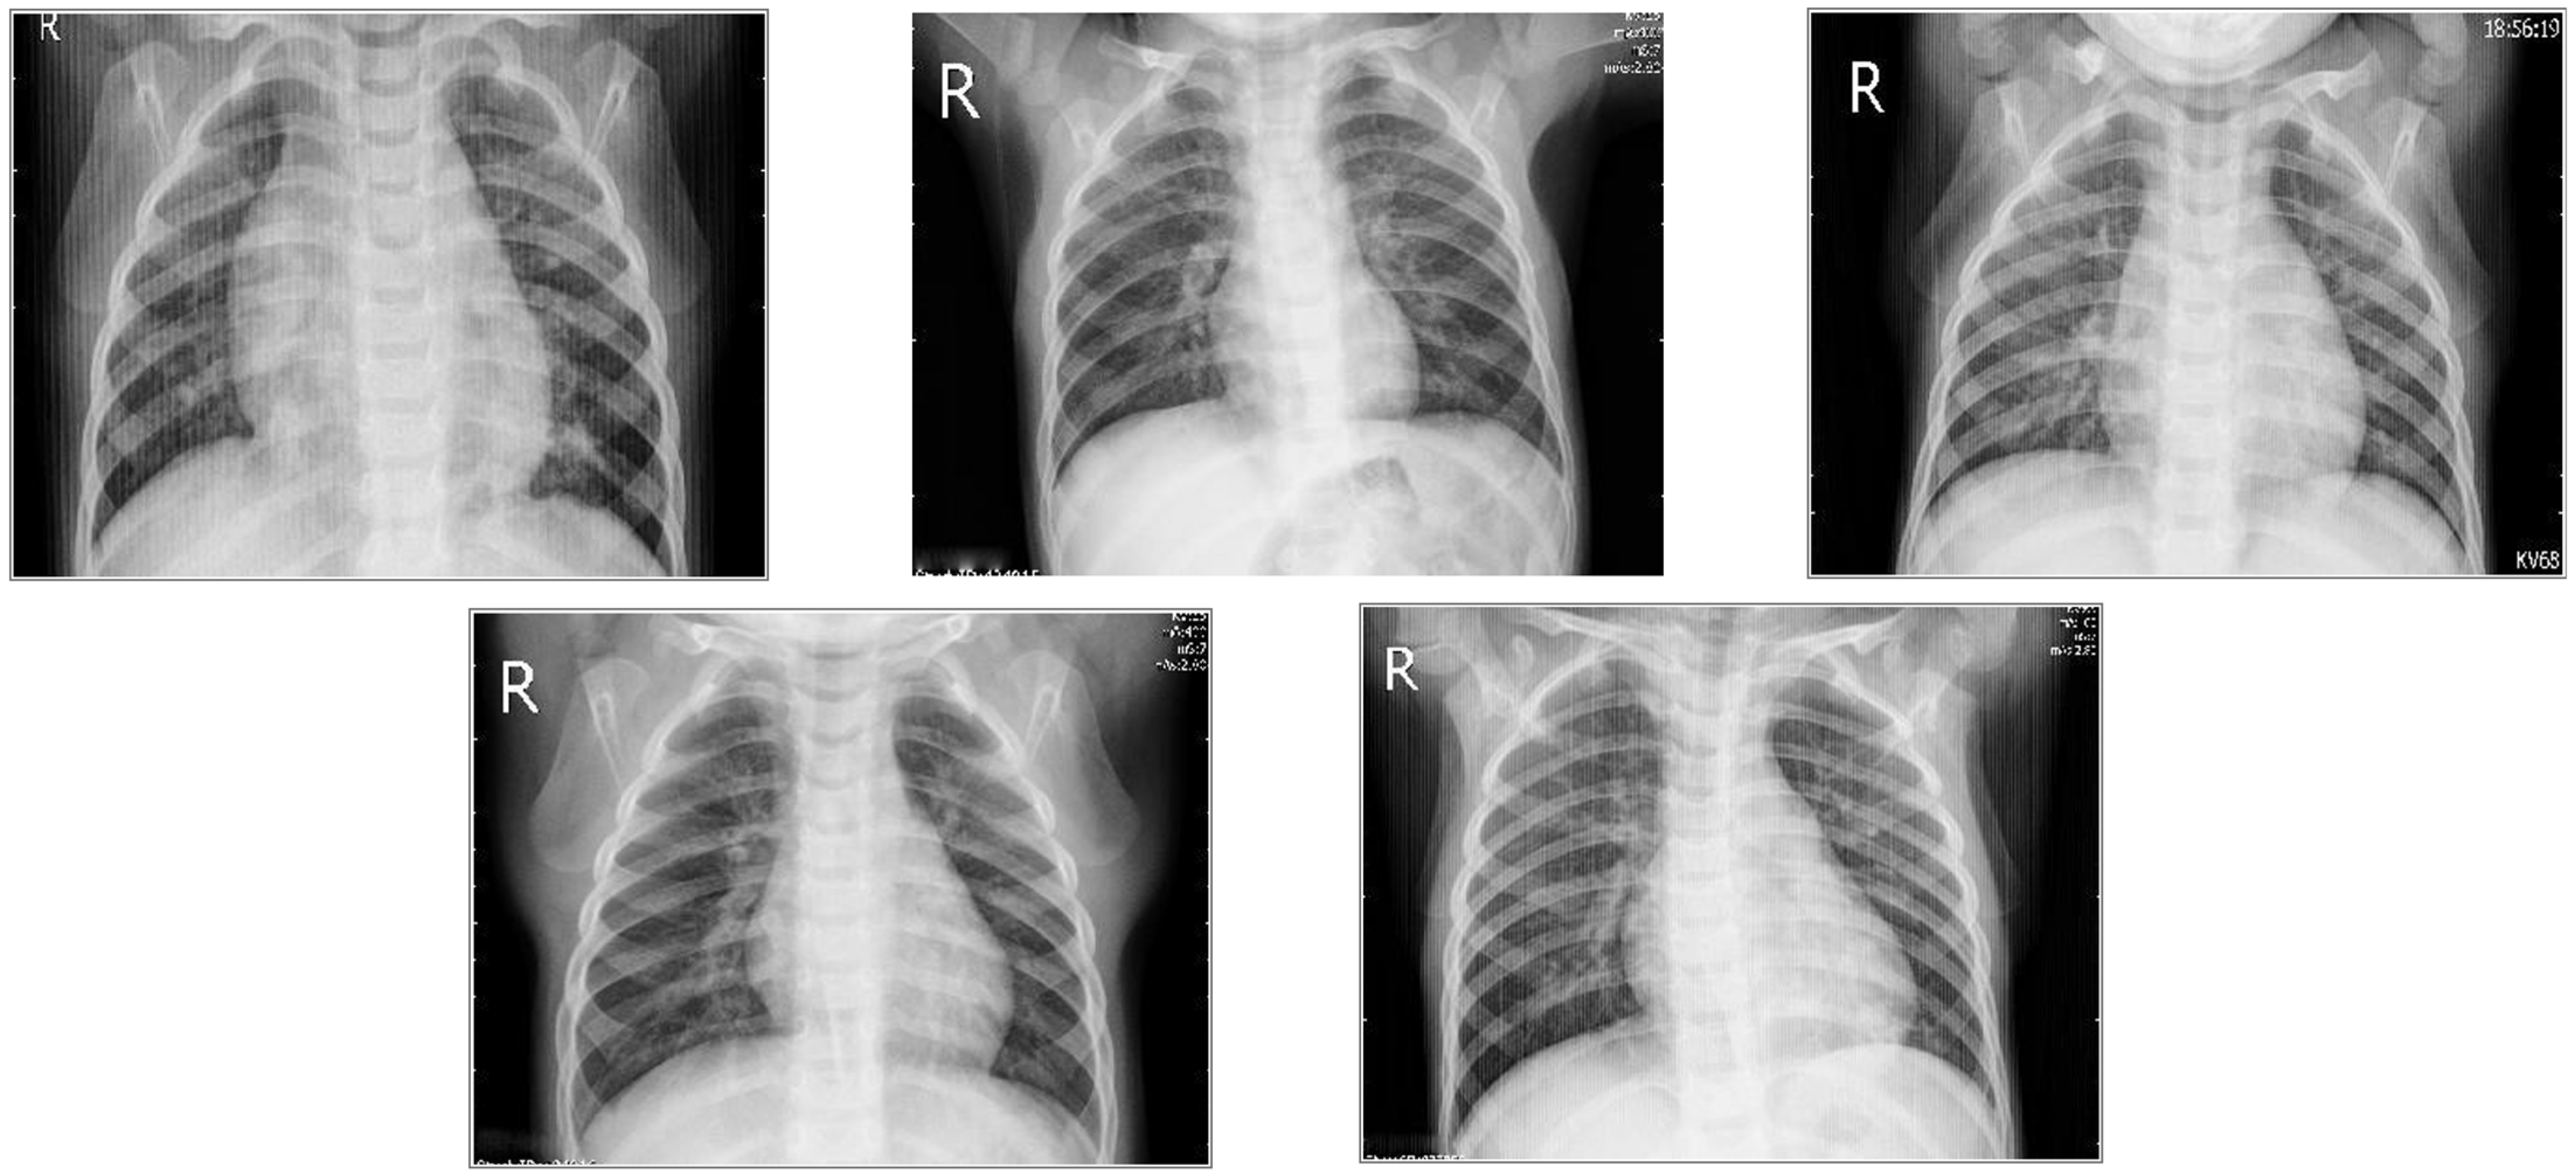

2.1.2. Chest X-Rays

| Pneumonia | 5850 | 2 | 768 × 1024, 500 × 700 | |

| Chest X-rays | 5847 | 2 | 768 × 1024, 500 × 700 | |

| 9203 | 4 | 300 × 400 | ||

| 7924 | 3 | 300 × 400 | ||

3.2.3. Pediatric X-Rays Pneumonia Model